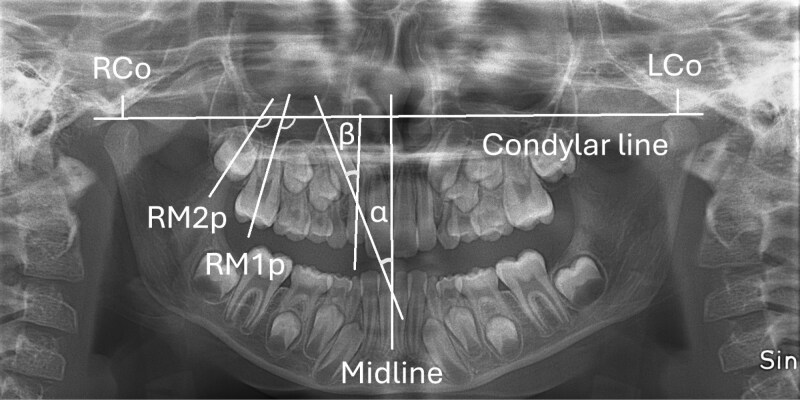

Methods: The material consisted of 67 seven-year-old children, with a Class II malocclusion, randomized into two equal-sized groups using opaque sealed-envelope randomization. In the early group (EG, n = 33), CH treatment was started at the age of 7.8 (T0) and in the later group (LG, n = 34) at the age of 9.5 (T1). Children received active CH treatment until Class I molar occlusion was achieved, after which individualized orthodontic treatment was provided at timepoints T2-T4. Dental panoramic tomographs (DPTs) were taken at five timepoints: T0-T4 (T0 = mean age 7.3 years, T1 = 9.6 years, T2 = 11.5 years, T3 = 15.3 years, and T4 = 17.8 years). The comparisons between the groups in DPT measurements were made at different timepoints using t-test and Mann-Whitney U-test and by combining the results using a linear mixed model. Due to the nature of the trial, the clinicians and children could not be blinded during the study; therefore, blinding was applied during data assessment.